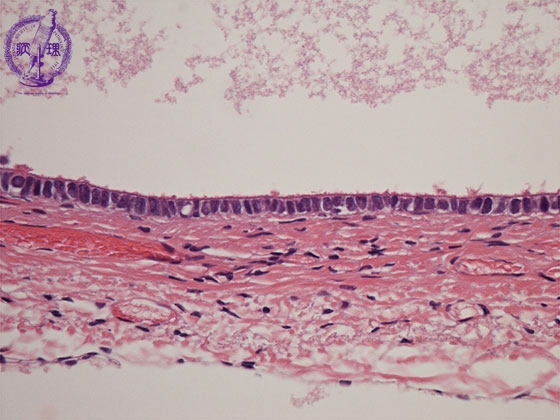

Histology (HE stain, high power): Serous cystadenoma of the ovary. Single layer of ciliated columnar cells (yellow dotted line) in inner surface of cyst.